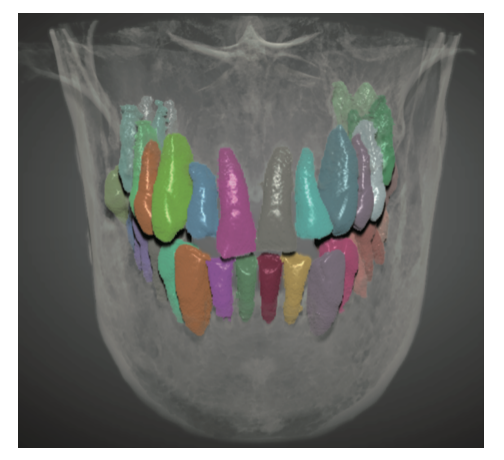

图:作者研究领域案例

作者杨慧芳在北京大学口腔医院以口腔医疗大数据和人工智能技术为重点研究方向。在教学方面,她主要研究教学、力学导航系统,如教学机器人、临床手术机器人以及医院服务机器人。此外,她还参与了智能健康管理、大众健康和疾病预防、医学图像的自动分割及识别等众多领域的研究,曾与清华大学、科大讯飞公司共同开发基于语音的口腔电子病历系统。

图:书中介绍界面和展示编程效果的内容

另外,书中的六个案例均源自临床,囊括了口腔、心血管、肺部、肾脏等不同科室,作者对此进行了详细的剖析,每个案例都套用书中的流程模板展开,包括图像导入、图像标注、训练模型、数据增强、图像匹配等流程,在实例中巩固对流程的掌握,在运用流程中增加对实例的理解,既有实践参考意义,也更有助于读者快速上手。